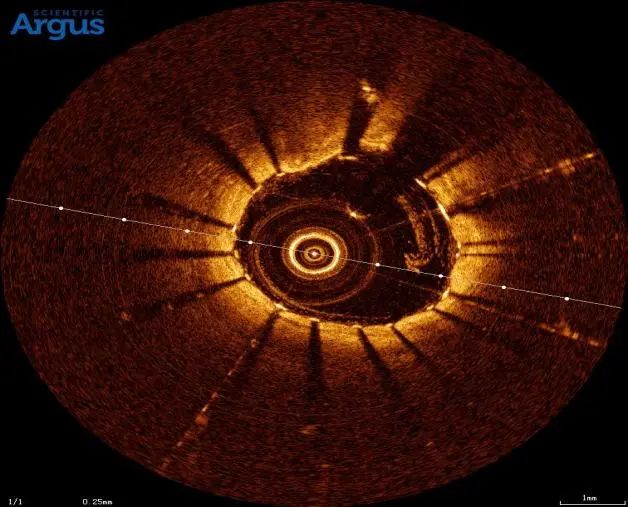

患者张女士,70岁,主因发作性剑突下疼痛6小时入院。入院诊断:冠状动脉性心脏病 急性下壁ST段抬高型心肌梗死。冠脉造影显示冠脉右冠中段钙化,且近段可见明显钙化影。孙彦博教授团队应用冠脉腔内影像学技术OCT对该血管进行了进一步的评估,结果显示:右冠中段可见360°环形钙化,此种情况极易造成支架膨胀不全。据此选择3.0×12mm Shockwave IVL冲击波球囊对中段钙化病变进行3个周期的预处理,应用OCT进一步评估显示严重钙化处出现钙化断裂,此种情况预示支架植入后可以获得满意的支架膨胀效果。果然,根据支架后OCT结果显示右冠中段严重钙化病变处支架膨胀率达108%,达到了理想的支架膨胀结果。

患者冠脉造影图像及OCT显示360°环形钙化

使用IVL血管内冲击波技术处理钙化病变 4atm 震动3个周期。OCT显示可见明显钙化断裂带。